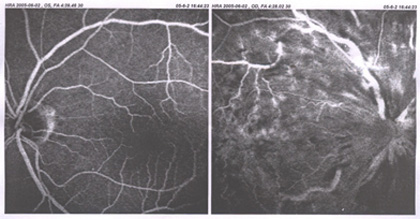

视网膜中央静脉阻塞

眼睛,中华眼科在线,视网膜,静脉阻塞,眼病,图谱